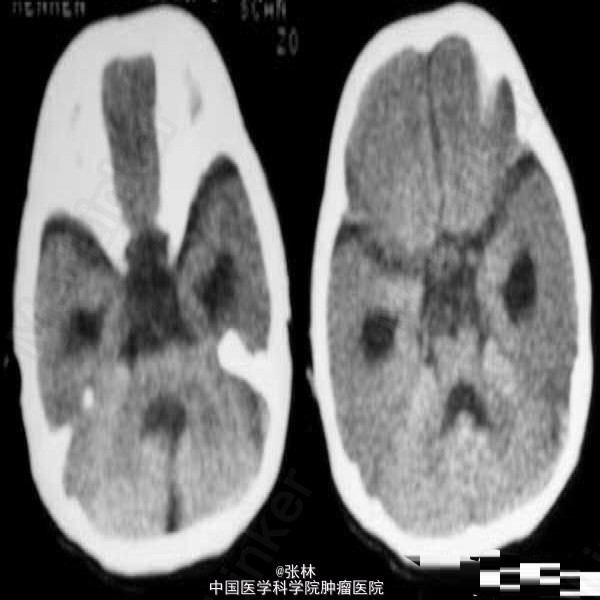

【临床病史】:患儿,F/0.5Y。癫痫,近一个月来频发。五官尚可,头颅大小与同龄儿相比稍小,智力低下(平时家人逗小孩时目光及动作迟缓)。 【影像表现】:显示双侧大脑半球皮层明显增厚、表面光滑、无脑回及脑沟,皮层下白质稀少。双侧外侧裂变浅、凹陷,整个双侧大脑半球呈“8”字形表现,脑室系统扩大。前纵裂增宽、增深,与第三脑室向连通。双侧侧脑室扩大、分离。 【影像诊断】:无脑回畸形伴胼胝体发育不良(Lissencephaly associated with Corpus Callosum dysplasia) 【诊断要点】:无脑回畸形伴胼胝体发育不良 【讨论】:无脑回畸形和/或巨脑回畸形:无脑回畸形指大脑表面光滑,无脑回结构;巨脑回畸形指大脑停留在原始阶段,脑回宽、扁。两者仅为畸形成度不同,可同时存在于脑的不同部位。前者多在顶枕部,后者多位于额部。镜下管前者大脑皮质结构异常,皮质分层不完全或不分层,常见不成熟的神经细胞。后者皮层保留了原始皮层的4曾神经细胞结构,神经细胞分化不成熟。白质中常发现异位的神经细胞,有时呈结节状。 [临床表现] 无脑回畸形患儿在新生儿期常有小头畸形和轻微面部异常,以后表现出智力落后。完全性无脑回畸形者大多在2岁前死亡。巨脑回存活者常有智力低下和癫痫。 [CT表现] 无脑回畸形和/或巨脑回畸形,前者主要表现为脑表面光滑,脑回、脑沟消失,皮层增厚,白质减少。后者主要表现为侧裂变浅、增宽,脑回增宽,皮质增后,内表面光滑,白质减少,患侧脑室系统扩大。此外,无脑回畸形两侧裂变浅,呈“8”字形表现。